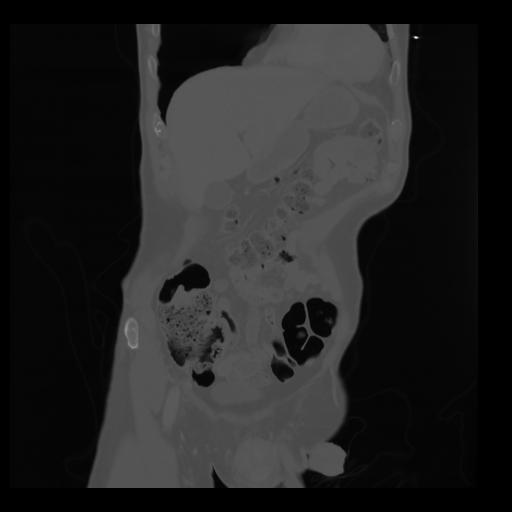

35 CUERPO,CE,Coronal,3.000,CUERPO,Coronal,